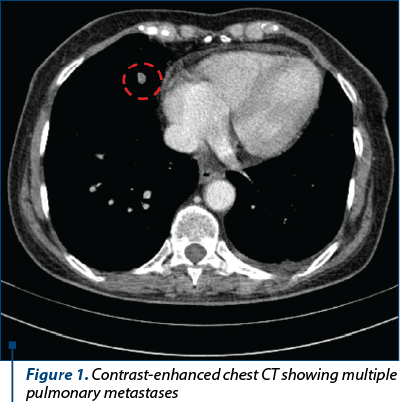

A computed tomography (CT) scan with intravenous contrast revealed a solid mass with malignant features located on the left kidney, multiple enlarged lymph nodes, and pulmonary metastases – cT3N1M1(pul) (Figures 1 and 2). The patient underwent radical left nephrectomy and para-aortic lymphadenectomy on January 17, 2018 (Figure 3). The pathologic study revealed papillary renal cell carcinoma (pT4pN1M1pul,lym) with subsequent immunohistochemical (IHC) results, as follows: PAX8 (+), vimentin (+), CD10 (+), AMACR (+), WT1 (-), calretinin (-).

Figure 1. Contrast-enhanced chest CT showing multiple pulmonary metastases